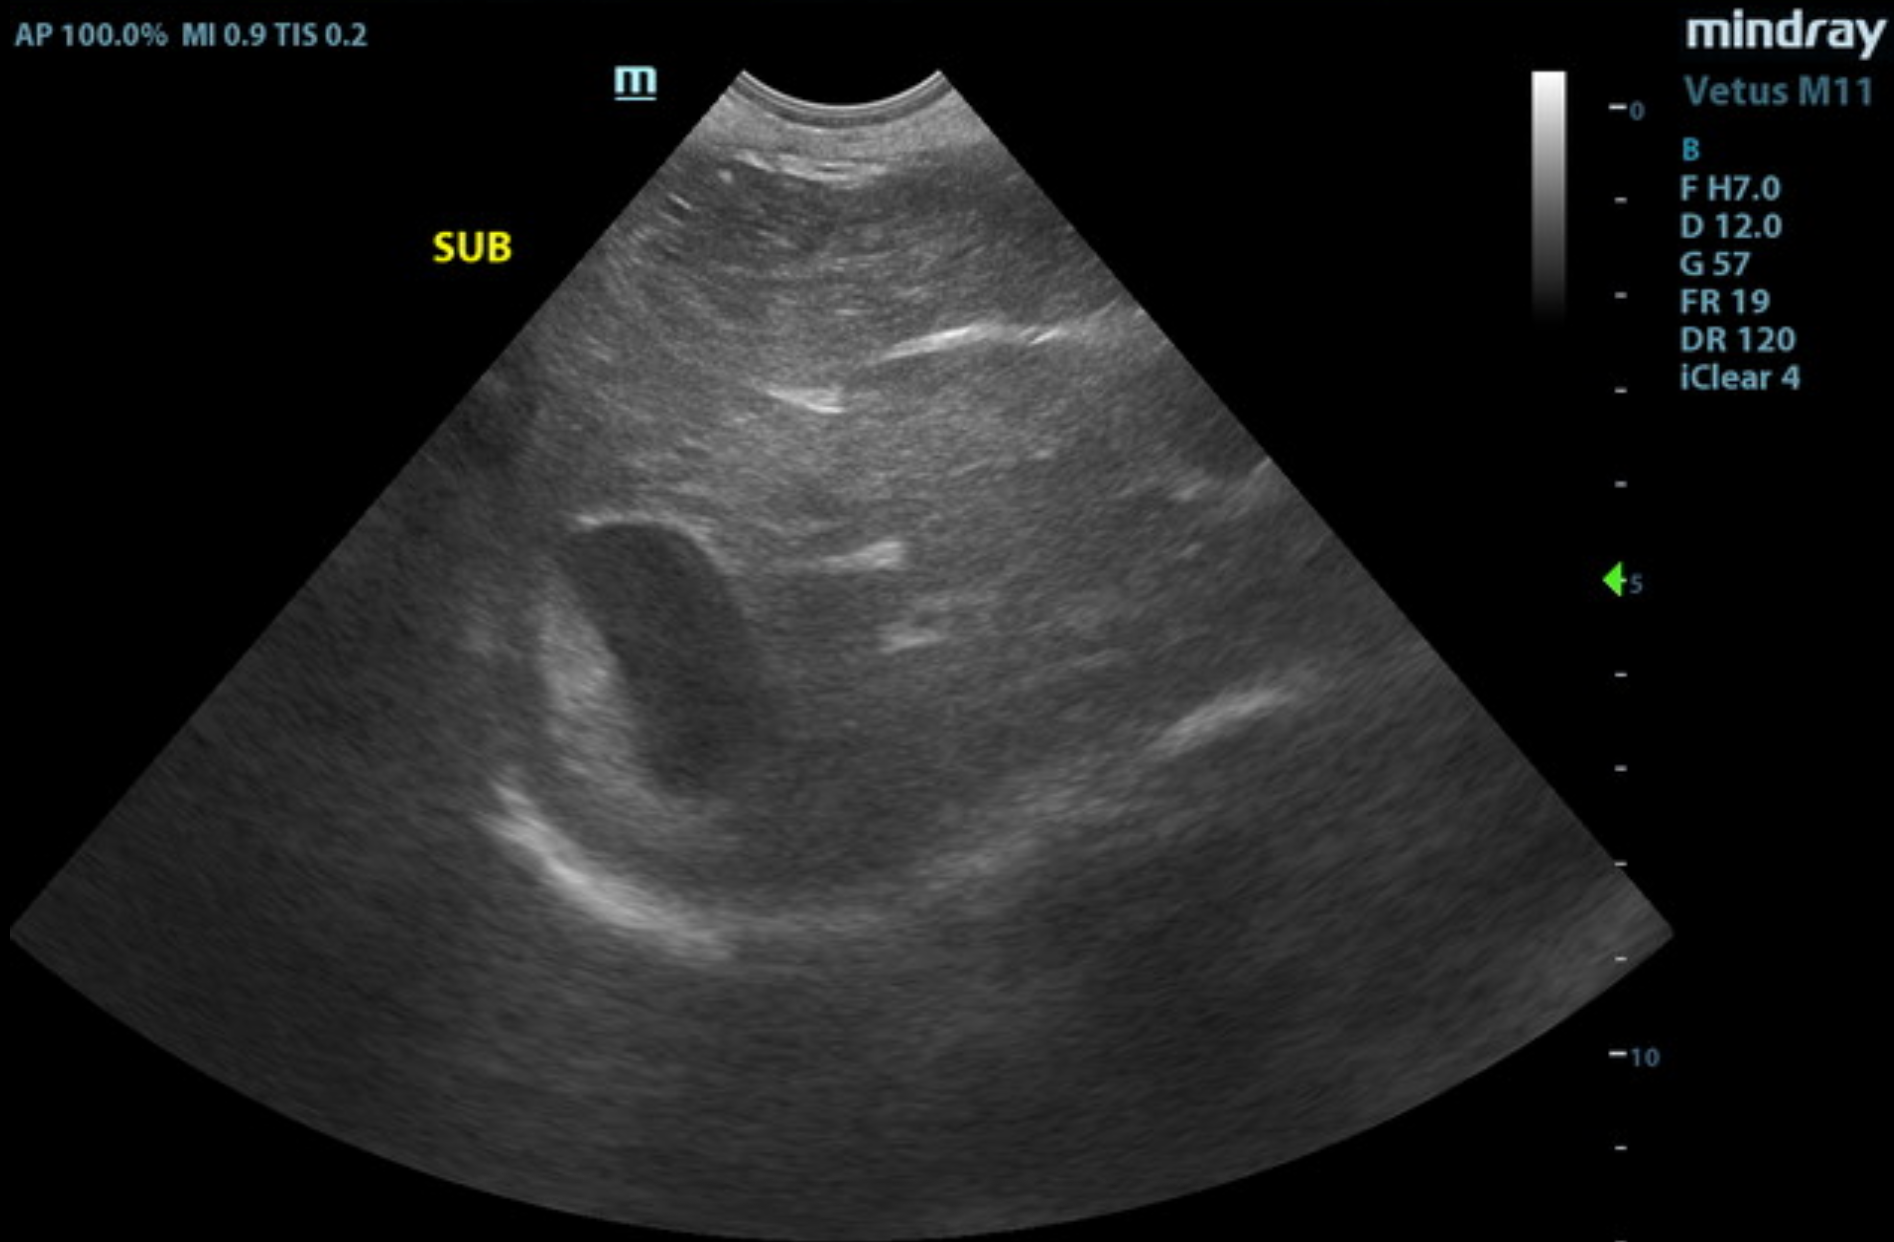

The liver images from right and left intercostal as well as subcostal views revealed subjectively normal liver size, contour, and structure. Some age-related parenchymal remodeling was noted but likely not clinically significant at this time. Vascular and biliary tracts were of normal volume, and no evidence of congestion was noted. The gallbladder presented some dependent debris with essentially normal contour. The cystic and common bile ducts were normal. No overt evidence of active inflammatory, infiltrative, or regenerative pathology was noted but should be paired with current or past LE elevations regarding any clinical significance to this presentation. The hepatic lymph nodes were unremarkable.